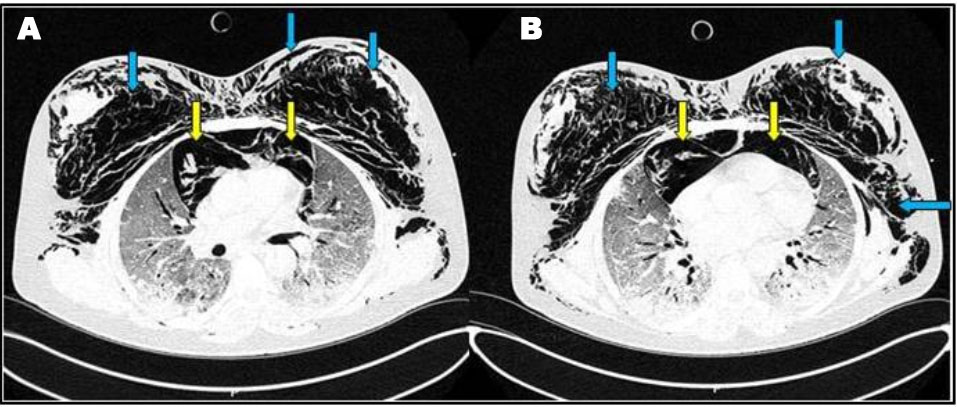

Figure 2: (A–D) Contrast-enhanced chest CT scan showing lower neck subcutaneous emphysema (yellow arrows), diffuse pneumomediastinum (red arrows), and diffuse bilateral ground-glass opacities (blue arrows).

A 65-year-old female patient with medical past history of obesity (body mass index (BMI) at 35 kg/m2), hypothyroidism treated by levothyroxine replacement therapy, was admitted in pulmonology department for confirmed COVID-19 pneumonia with two weeks history of fever, chills, asthenia, dry cough, and progressive shortness of breath, with initial non-contrast chest computed tomography scan (chest CT scan) showing bilateral peripheral ground-glass opacities and crazy paving with estimated percentage of lung involvement at 10% (Figure 1). She was managed initially with oxygen-therapy with nasal prongs associated to antibiotics, dexamethasone 6 mg/12 h, anticoagulation, hydration, and vitamins. On day four of admission, the patient developed a rapid onset of retrosternal chest pain associated to a moderate acute respiratory failure with severe hypoxemia: oxygen saturation (SpO2) of 88% under 15 L/min of oxygen with a non-rebreather mask. In front of the worsening of her state, she was transferred to our intensive care unit (ICU). Upon admission, her respiratory rate (RR) was of 35 breaths/min with struggle signs and hypoxemia and soft-tissue crepitus bilaterally. She was conscious with stable hemodynamic state. Laboratory tests revealed an elevated C-reactive protein (CRP) concentration of 53 mg/L (reference:<5 mg/L). Complete blood count showed a leukocytosis of 11.8×109/L (reference: 4–10×109/L), with lymphopenia (0.4×109/L). She had hepatic cytolysis with alanine aminotransferase (ALAT) and aspartate aminotransferase (ASAT) at 100 IU/L (reference:<45 IU/L) and 68 IU/L (reference: <50 IU/L) respectively. Serum level of D-dimer was at 457 µg/L (reference:< 500 µg/L). Arterial blood gas (ABG) showed a pH:7.41, PaCO2:43 mmHg, PaO2:74 mmHg, HCO3:27 mmol/L and PaO2/FiO2 ratio at 205. A contrast-enhanced chest CT scan was performed showing diffuse lower neck subcutaneous emphysema associated with diffuse PM and diffuse bilateral ground-glass opacities with posterior and peripheral predominance associated to alveolar consolidation with estimated percentage of lung involvement at 90% consistent with critical COVID-19 pneumonia (Figure 2A, Figure 2B, Figure 2C, Figure 2D). Urgent mediastinal decompression with chest drainage tube wasn’t immediately indicated in front of the maintained stable hemodynamic state, so we decided the conservative therapy with reduced airway pressure with non-invasive ventilation (NIV) [pressure support (PS) of 12–14 cmH2O, positive end expiratory pressure (PEEP) of 4 cmH2O, and fractional inspired oxygen (FiO2) of 100%]; awake prone positioning and close monitoring. Initially we obtained a slight improvement of his respiratory state. At day 7 of ICU stay she was intubated in front of NIV failure. The patient was ventilated with protective ventilation with volume assist-control ventilation mode (VAC mode) [tidal volume (Vt) at 6 mL/kg predicted body weight (PBW), PEEP at 4 cmH2O: low level in front of the PM, respiratory rate at 30 breaths/min and 100% of FiO2. She was immediately put under continuous infusion of sedation and neuromuscular blockers. Despite protective ventilation with lower pressure, there was a maintained severe hypoxemia, and the patient passed away due to refractory hypoxemia few hours later.